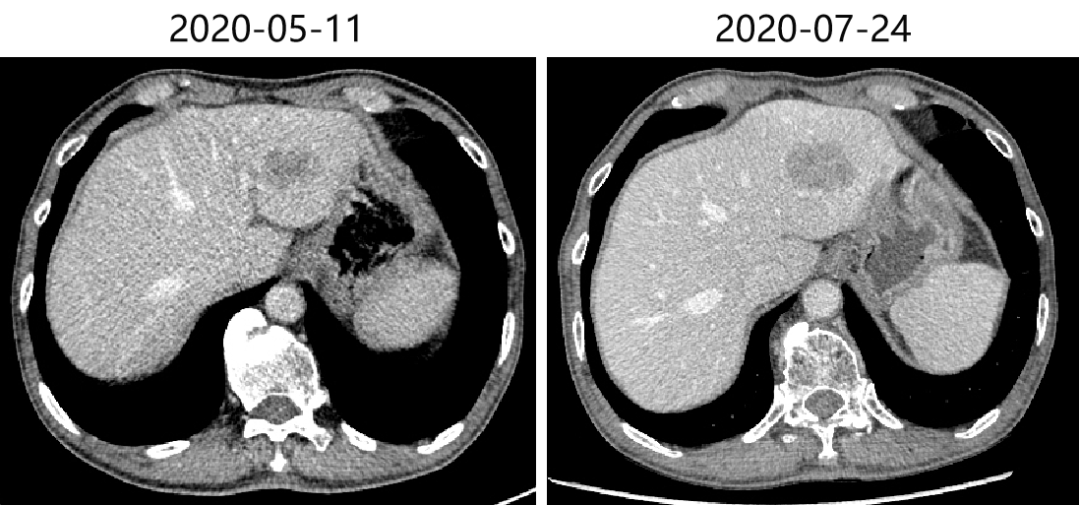

2019-11-11、2020-03-10、2020-05-11 复查CT评价SD。

头胸腹盆增强CT(2020-07-24)示:双肺多发结节,部分较前(2020-05-11)明显增大,考虑转移灶;肝左叶占位,考虑转移,较前(2020-05-19)增大;考虑病情进展。

肺:肺部多发结节,部分较前(2020-05-11)明显增大,考虑转移。考虑PD。

肝:肝左叶占位,考虑转移,较前(2020-05-11)增大;考虑PD。